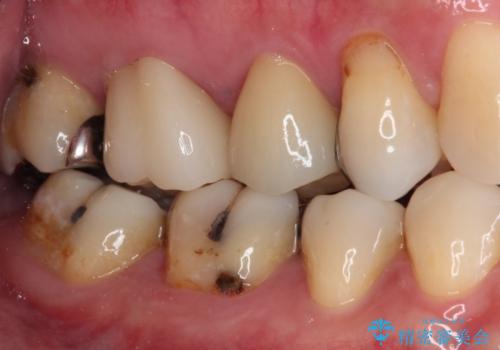

- 奥歯に強い痛みを感じるとのことで来院された患者様です。

診査したところ、既に根管治療されている大臼歯の咬合痛と、神経の残っている手前の小臼歯の強い冷熱痛を認めました。

神経の残っている小臼歯は神経を取り除く必要があったため、速やかに根管治療を行うこととしました。

隣に位置する既に根管治療されている大臼歯は、手前の小臼歯の痛みが波及している可能性も考えられたため、小臼歯の根管治療後に改めて診査をした上で治療方針を定めることとしました。